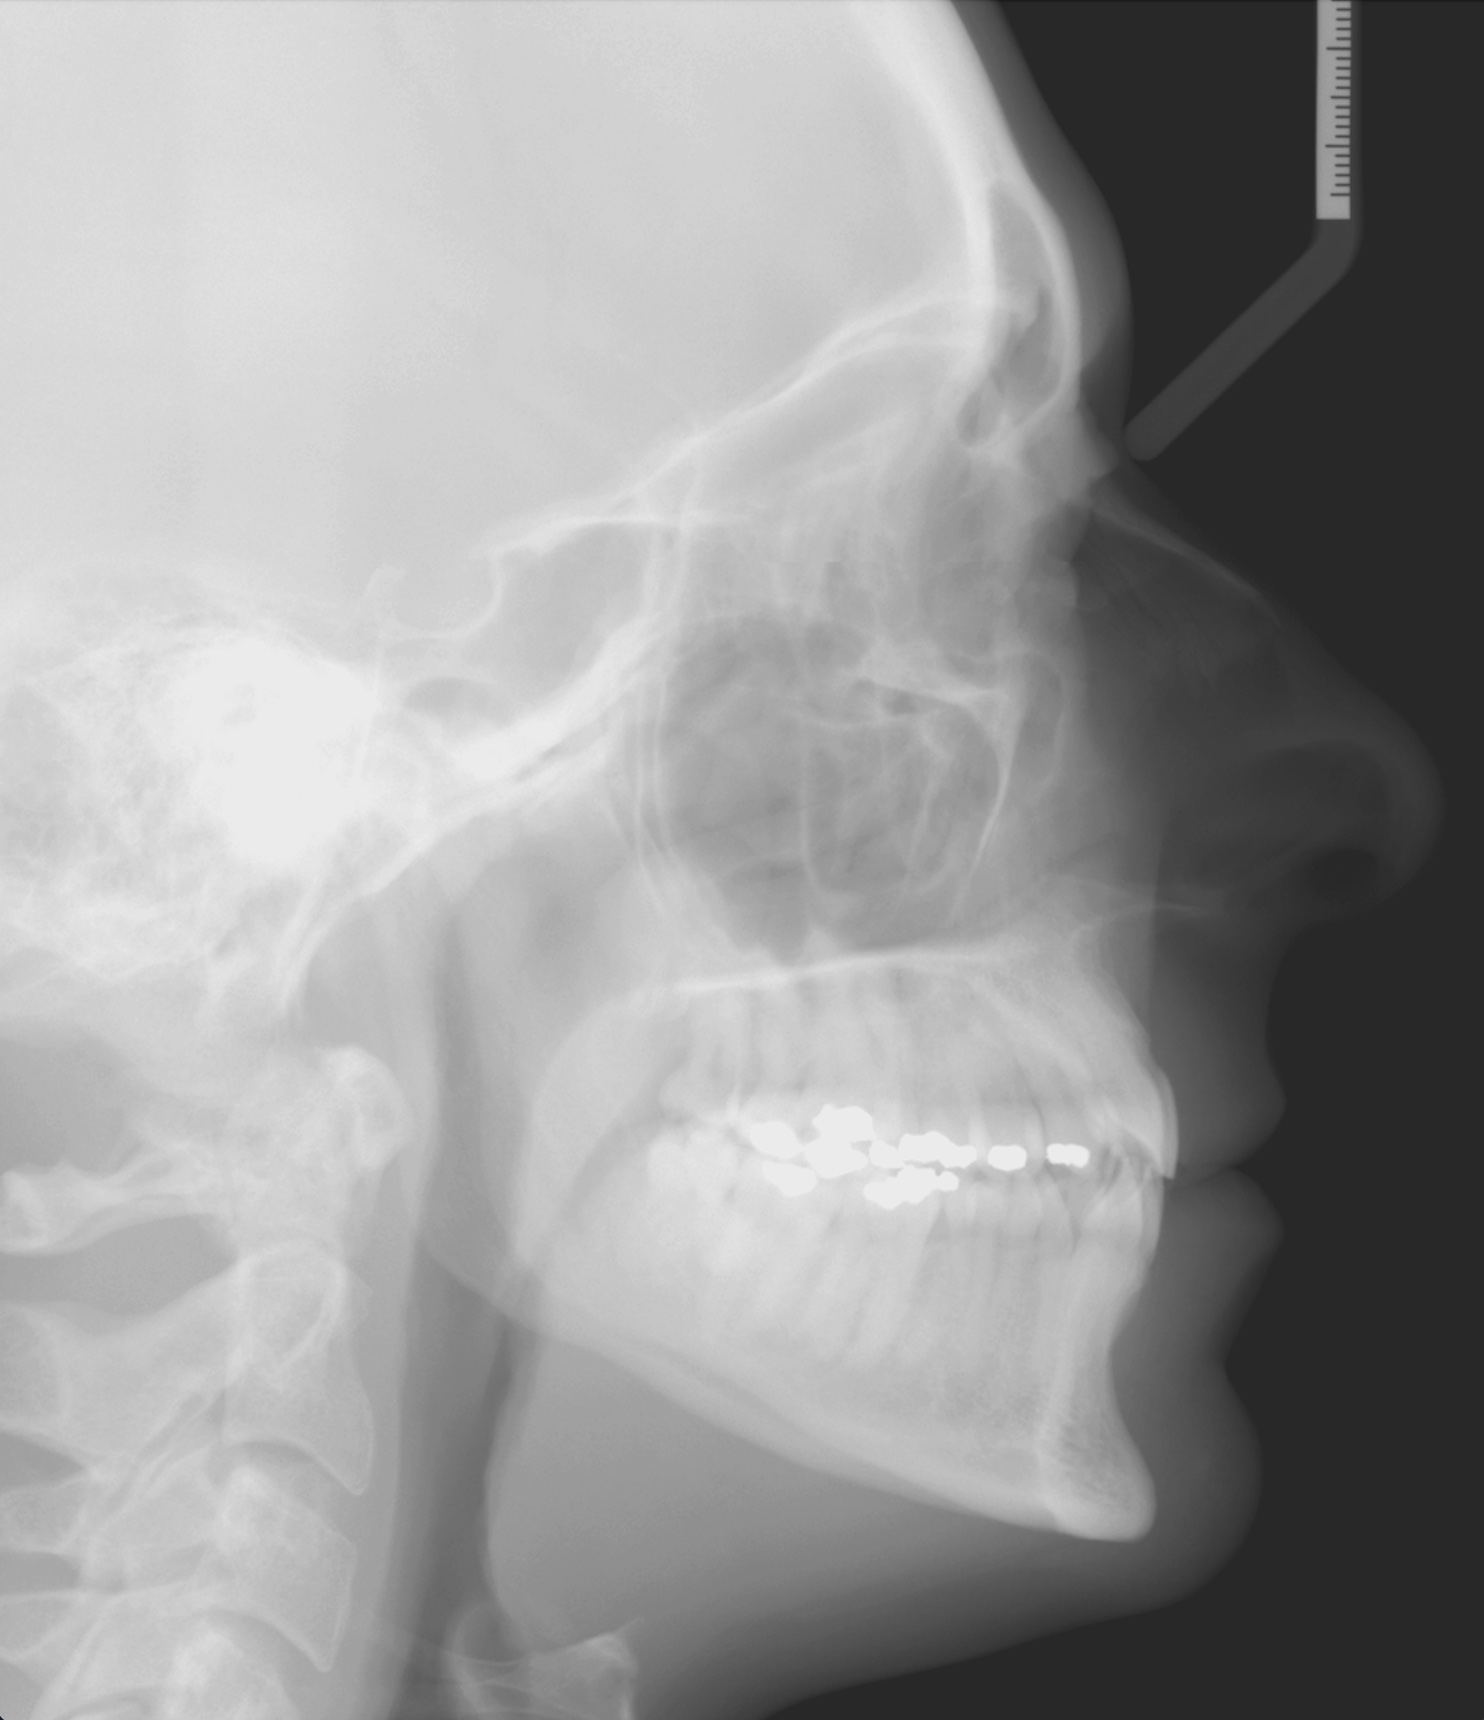

Per formulare corretta diagnosi e piano di cura, lo studio del caso ha previsto la raccolta di documentazione completa standard, ovvero fotografie del viso e intraorali (Figure 1a-e), radiografia panoramica e teleradiografia del cranio in proiezione laterale (Figure 2a-b) per la relativa analisi cefalometrica e modelli di studio.

La valutazione clinica e gli esami effettuati confermano la presenza di agenesia degli incisivi laterali superiori (1.2 e 2.2) e del secondo premolare inferiore destro (4.5).

L’analisi ortodontica e la valutazione parodontale, con particolare riferimento alla posizione della radice del canino superiore destro (1.3), distoinclinata e trasposta alla radice del primo premolare (1.4) come evidente dalla radiografia panoramica e dalle immagini intraorali, ci hanno guidati nella programmazione di un trattamento estrattivo asimmetrico a entrambe le arcate.